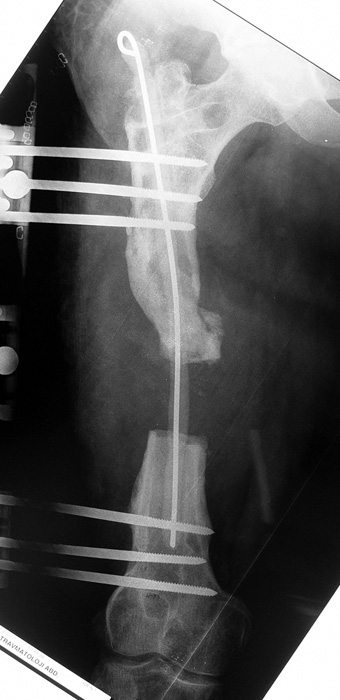

Appropriate radical debridement necessitates excision of all necrotic bone and soft tissues, and frequently causes instability at the involved extremity. The remaining bone and soft tissue defect has to be fixed and reconstructed. The distraction osteogenesis method of Ilizarov is used successfully for achievement of union, correction of the deformity, elimination of limb length inequality and reconstruction of segmental bone defects.

The duration of external fixation (external fixation index) depends on the amount of distraction required, and the extremity is prone to complications during this period. After the distraction phase is completed, the external fixator remains in place during the consolidation phase, which lasts twice as long as the distraction phase; but this period is hardly tolerated. If the external fixator is removed before sufficient consolidation is achieved, fractures, deformity and shortness will be the result. In our department, ‘lenghthening over nail’ method is used in order to decrease the external fixation index and increase patient comfort and activity level. In this method, the intramedullary nail is statically locked after the completion of the distraction phase, and external fixator is removed. The extremity is stabilized by the intramedullary nail during consolidation phase. In this way, complications due to long external fixation index or early removal of the external fixator are avoided.

Case 3